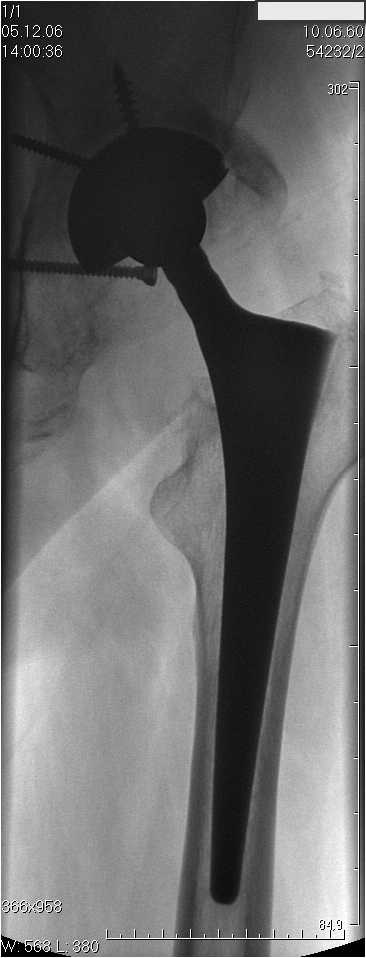

Уважаемые коллеги.В 3 Центральный Военный Клинический Госпиталь имени А. А. Вишневского, что в Красногорске, Московской области, в отделение эндопротезирования крупных суставов поступил пациент 1960 года рождения Жалобы при поступлении: на боли в области левого тазобедренного сустава (больной указывает на точку расположенная в середине условной линии между седалищным бугром и большим вертелом), усиливающиеся в начале ходьбы, при опоре на левую ногу с иррадиацией болей по наружной и наружно-задней поверхности левого бедра, левый коленный сустав; снижение объема движения в левом тазобедренном суставе, снижение опорной способности левой нижней конечности, хромоту на левую ногу, необходимость использования дополнительной опоры (костыли) при ходьбе, снижение объема двигательной активности из за болей в суставе.В анамнезе: Со слов больного, согласно медицинских документов, в 1989 году получил травму левой нижней конечности: закрытый перелом левой вертлужной впадины с центральным вывихом головки левой бедренной кости. Лечился консервативное. В процессе лечения сформировался посттравматический артроз, укорочение левой нижней конечности до 5 см. 25.04.2005 года в Подольском Окружном Госпитале Министерства Обороны выполнено: одномоменто, остеосинтез заднего края вертлужной впадины фрагментом резецированной головки бедренной кости и тотальное эндопротезирование левого тазобедренного сустава бесцементным эндопротезом "VERSIS ET" с бесцементной чашкой TRILOGY. Послеоперационный период осложнился ранним нагноением области эндопротеза, в результате санаций очага инфекции и антибиотикотерапии, активного промывного дренирования антисептиками, послеоперационная рана зажила. После операции, со слов больного, через два месяца в полном объеме стал нагружать левую нижнюю конечность. В течение полгода, после операции чувствовал себя вполне удовлетворительно. С марта 2006года стал отмечать появление болей в области тазобедренного сустава, то в области паха, то в области левой ягодицы. С августа месяца отмечает те жалобы, с которыми он сейчас к нам обратился. Температура тела, после заживления раны, нормальная. В анализах крови, лейкоциты около 7 тыс, формула нормальная, СОЭ 12 мм ч. Локально: при осмотре обеих нижних конечностей, анатомическая ось конечности не нарушена; отмечено относительное укорочение левой н\конечности на 1.5 см., гипотрофия мышц левого бедра 3 см, голени 2 см, симптом. Объем движений в тазобедренных суставах: правый~ сгибание- 60 гр, разгибание-180 гр ,отведение- 35 гр, левый~ сгибание- 110 гр , разгибание-170 гр , отведение-15 гр. Контуры других суставов н/конечностей обычные, объем движений в них не страдает. Пульсация на артериях конечностей удовлетворительная. Неврологические нарушения конечностей отсутствуют, рефлексы на обеих н/конечностях одинаковые, чувствительных нарушений нет. Осевая нагрузка на левую нижнюю конечность вызывает боль в точке расположенная в середине условной линии между седалищным бугром и большим вертелом. Отмечается пигментация и пастозность нижней трети обеих голеней и стоп, характерная для посттромботической болезни. На Цветном дуплексном сканировании сосудов нижних конечностей: Нестенозирующий атеросклероз обеих бедренных и подколенных артерий . Гемодинамически значимых препятствий кровотоку в магистральных артериях ног не выявлено. Глубокие и поверхностные вены нижних конечностей проходимы. Умеренная недостаточность клапанов подколенных вен. Данных за тромбоз глубоких вен на момент осмотра не получено.А вот что пишет наш рентгенолог: На серии рентгенограмм области левого тазобедренного сустава определяется тотальный бесцементный эндопротез. Вокруг тени чашки эндопротеза определяется ободок остеорезорбции. Кроме того, визуализируется деформированный костный винт фиксирующий консолидированный отломок вертлужной впадины, вплотную прилегающий к тени чашки эндопротеза. Заключение: Рентгеновские признаки нестабильности чашки тотального эндопротеза. Лучевая нагрузка: 6 мЗв. У нас в отделении разошлись мнения: начальник мой утверждает, после сравнения снимков, принесенных больным от августа и октября 2006года и наших рентгенснимков, что у больного нет нестабильности вертлужного компонента, и что надо назначит курс консервативной терапии: препараты кальция, миакальцик, увеличить осевую нагрузку на левую нижнюю конечность, ЛФК направления на укрепление мышц бедра, ягодиц, физиолечение. А я утверждаю, что у больного клиника нестабильности вертлужного компонента, и необходима ревизия вертлужного компонента, не исключено даже наличие инфекции под чашкой эндопротеза (не смотря на отсутствие клинических признаков инфекции). В результате проводимой консервативной терапии, боли у больного усилились. Помогите рассудить нас, мы готовы выслушать ваши мнения по этому поводу. С уважением Батал Шушания.3 ЦВКГ имени А. А. Вишневского

Ув. Коллега.Четких рентгенологических признаков нестабильности вертлужного компонента действительно нет. Здесь, кроме нестабильности, можно искать причину в поясничный отдел позвоночника(Hip-spain синдром - всё-таки 15 лет ходил с укорочением),либо сделать спиральный КТ и посмотреть, нет ли несращения в области старого перлома вертлужной впадины. Зачастую ложные суставы подвздошной, седалищной, а иногда и лонной костей являются причинами несостоятельности эндопротезов.

Уважаемый д-р Батал,

Ситуация не столь однозначная как Вам это видится. По подробно описываемой клинике с большей вероятностью речь идет о проблемах

поясничного отдела позвоночника. Есть зона остеолиза вокруг чашки, но как правило, дополнительный винт держит чашку достаточно хорошо, и даже при наличии микроподвижности, это не сопровождается столь ярким болевым синдромом. Поэтому, я бы сделал следующее: МРТ позвоночника, пункцию ТБС для исключения инфекционного процесса. Ревизию рассматривал бы как крайний вариант, учитывая выполненную костную пластику и отсутствие явных признаков нестабильности.

уважаемый коллега, Антон Вакуленко. Спасибо за четкий, расписанный по пунктам план действий. При поступлении пациента в отделение, я думал точно как вы. Но на следующий день, выполнил многопроеционное рентгенисследование, показал невропатологу, и доложил начальнику отделения о больном.После разбора пришли к следующему, да у больного действительно нестабильность вертлужного компонента, есть зона лизиса в месте костного аутотрансплантата, а в месте фиксаци чашки деротационным винтом четко выраженный контакт чашки с костной тканю. Мы пришли к выводу,что лизис костного аутотрансплантата из за осевой перегрузки на фоне незавершенного ремоделирования (вес больного 130 кг). Потому мы и приняли план вышеуказанного лечения. Провели беседу с больным, больной согласился с нами. Через 3-6 месяцев мы оценим эффективность лечения и доложу. Возможно и придется тогда идти на ревизию с заменой только вертлужного компонента а может и придется удалить весь эндопротез с установкой спейсера.. посмотрим.....

> компонента, есть зона лизиса в месте костного аутотрансплантата,

> а в месте фиксаци чашки деротационным винтом четко выраженный

> контакт чашки с костной тканю. Мы пришли к выводу,что лизис